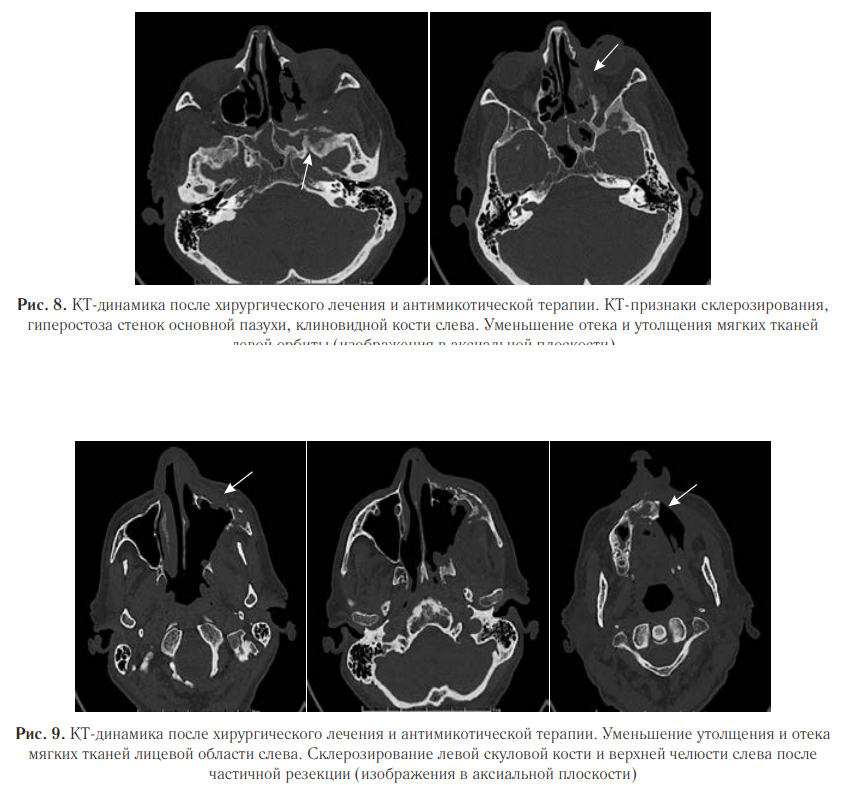

Также были выявлены деструктивные изменения верхней челюсти с утолщением и эмфиземой мягких тканей лицевой области слева (рис. 7). Пациент был переведен в специализированное отделение. Проведена секвестрэктомия верхней челюсти, удаление зубов слева. В гистологических препаратах послеоперационного материала выявлены нити мицелия. При пересмотре гистологического материала в НИИ Медицинской микологии им. П. Н. Кашкина, был обнаружен широкий несептированный мицелий, характерный для мукоромицетов. На основании клинической картины, данных КТ и микологического обследования был диагностирован COVID-ассоциированный мукормикоз околоносовых пазух и структур орбиты. Назначили антимикотическую терапию: введение липосомального амфотерицина В 10 мг/кг в сутки, после стабилизации состояния переход на пероральную терапию. По месту ведения пациента была начата антимикотическая терапия липидным амфотерицином В 14 дней, далее амфотерицином В дезоксихолатом, который был отменен ввиду нефротоксичности. В последующем лечение продолжили изавуконазолом в стандартной дозе. Согласно международным рекомендациям, проводился контроль уровня глюкозы крови и произведена отмена ГКС. Общая продолжительность лечения составила 105 дней. Ежедневно в первую неделю, затем по мере необходимости проводили осмотр области оперативного вмешательства с местной обработкой слизистых оболочек препаратами амфотерицина В. После проведенной антимикотической терапии на контрольных МСКТ ОНП выявили признаки стабилизации мукормикоза в виде отсутствия прогрессирования процесса; склерозирования, утолщения и гиперостоза костей; уменьшения отека и утолщения мягких тканей с их фиброзированием (рис. 8, 9).